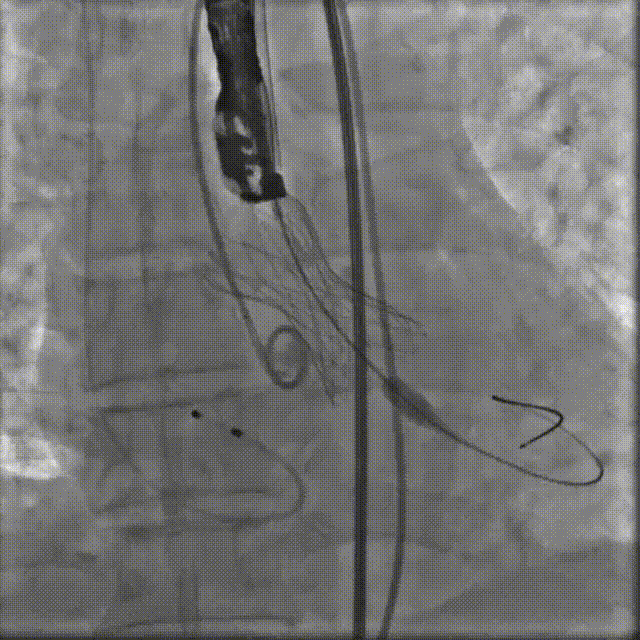

TaurusElite AV29号瓣膜定位及释放。瓣膜初始定位-3位,开花后120次起搏,释放到工作位后造影显示锚定充足,位置良好,冠脉未见遮挡,继续缓慢旋转手柄,轻推输送器,瓣膜逐一脱钩,顺利释放。

瓣膜初始定位

瓣膜释放过程

工作位造影

瓣膜脱钩